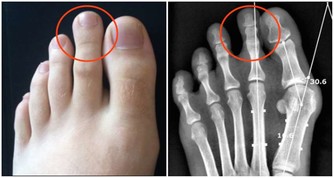

年紀日趨增長,身體的代謝也就越來越緩慢,因此許多男性只要到了中年,飲食習慣依舊維持著大魚大肉,可就容易挺著一身鮪魚肚。然而對於男性來說肚子變大、無故隆起,似乎都是因為肥胖的關係而造就啤酒肚出現,不過最近這則新聞的出現,可是讓人看到「啤酒肚」的產生,不一定是變胖的關係,反而有可能是自己的身體出狀況、長腫瘤!

這名捷克的男子Josef Martinec最近挺著一身「大肚子」前往醫院就醫,原本以為是中年發福的關係,造就自己身體不適,不過待醫生詳細的檢查完,才赫然發現到他的腹部裡藏著一顆重達27公斤(60磅)的惡性腫瘤,不得不趕緊開刀切除。

原來Josef是因為最近出現背痛、呼吸不順的症狀,才趕快赴往醫院檢查,起初他以為是肥胖因素導致身體出狀況,不過到院檢查後卻發現是肚子裡長著一顆腫瘤,大到已經擠壓到附近的器官:腎臟、肝臟與肺部,為求保命在醫生的建議下立即動手術移除腫瘤。

最後這場手術歷經六小時才成功切除腫瘤,待醫生一秤之下才知道這顆腫瘤重達27公斤。

術後的Josef仍須住院六個月積極治療,由於腫瘤與病人的腹部其他組織有相連,因此醫生也不敢大膽預測他的往後的病情會是如何,據了解,類似的大腫瘤病況在捷克境內相當罕見。